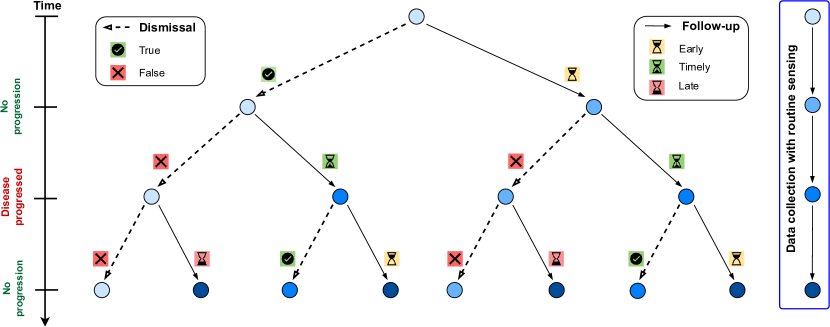

Our objective is to make optimal, w.r.t. both costs and outcomes over a defined time interval , sequential decisions to refer each subject for an examination, to capture the disease progression using the acquired multi-modal data. We illustrated the decision-making process in Figure 2. Specifically, for each subject, at time point , we predict whether that subject should be examined at the next time point . The referral for an examination is considered successful if the disease has progressed between and . We formalize this as the following optimization problem:

For each subject, at time point , an agent takes one of two actions – to follow up or to dismiss (i.e. skip examination) at time . The rewards for these actions are denoted as and , respectively. The reference point is updated to the latest visit, ensuring that the reward calculations are based on the most recent state of the subject’s condition. By comparing with – the nearest progression time point extracted from the patient-level progressions set , we derived five possible scenarios. Namely, there are three cases for the correctness of the follow-up action (): early visit, timely visit, and late visit and two cases for the one of the dismissal action (): true dismissal and false dismissal.

Mathematically, the reward at the time point corresponding to the follow-up and dismissal actions can be expressed as follows:

| (12) |

| (13) |

where is the data acquisition utility function, representing the cost of significant changes relative to , formulated as:

| (14) |

is the fixed cost of data acquisition. The reward for a late visit is equivalent to that for a false dismissal, yet discounted by and decreased by . In addition, is the positive reward for the correct dismissal action.

To incorporate the difference between the time of making decision and the true KOA progression time into the reward function, we introduce the modulating function , defined as:

| (15) |

As such, we consider two specific cases that require such a modulating function: early follow-up and late follow-up/false dismissal. For the first case, we use an exponential decay function . Therefore, an increasing reduces the reward that an agent can obtain. For the second case, we penalize late or false dismissal actions and use the term . As increases, the negative reward becomes more considerable, discouraging the agent from delaying necessary actions or incorrectly dismissing the patient.